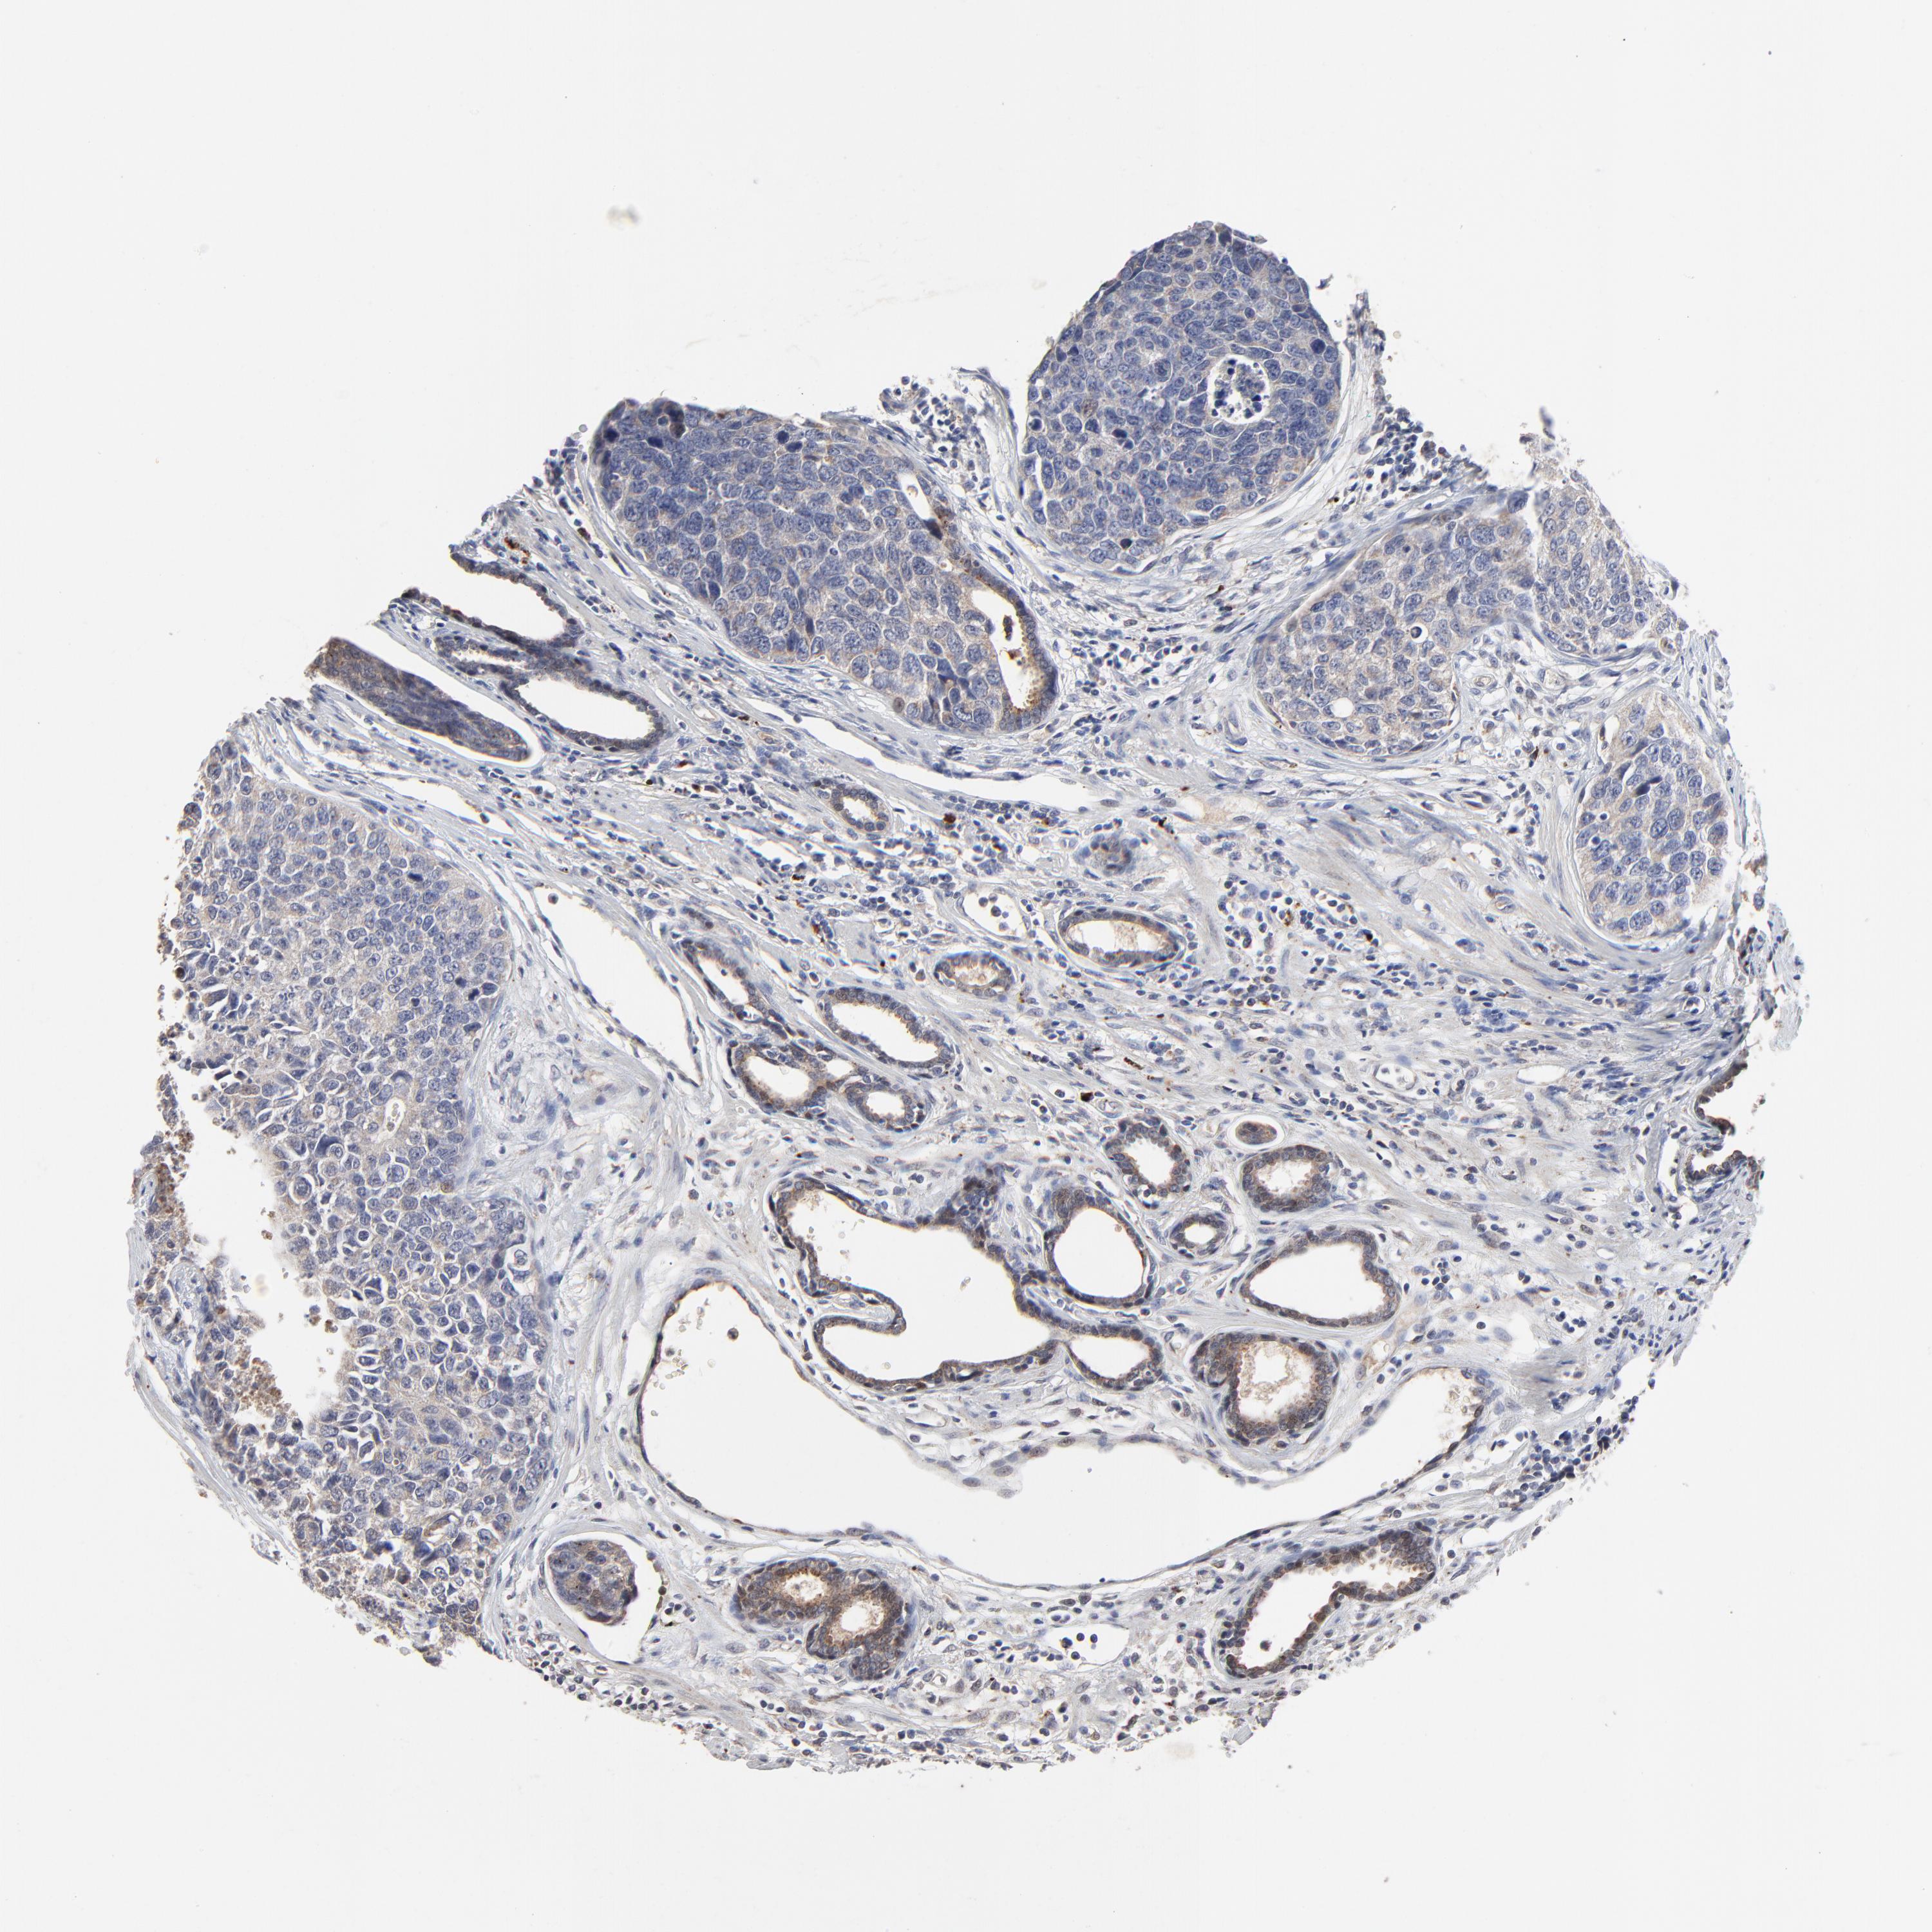

UROTHELIAL CANCER - Protein expressioni

A mouse-over function shows sample information and annotation data. Click on an image to view it in a full screen mode. Samples can be filtered based on level of antibody staining by selecting one or several of the following categories: high, medium, low and not detected. The assay and annotation is described here.

Note that samples used for immunohistochemistry by the Human Protein Atlas do not correspond to samples in the TCGA dataset.

Antibody stainingi

Antibody staining in the annotated cell types in the current human tissue is reported as not detected, low, medium, or high, based on conventional immunohistochemistry profiling in selected tissues. This score is based on the combination of the staining intensity and fraction of stained cells.

Each image is clickable and will lead to virtual microscopy that enables deeper exploration of all samples and also displays staining intensity scores, fraction scores and subcellular localization as well as patient and tissue information for each sample.

Antibody HPA003162

Antibody CAB005191

Staining

High

Medium

Low

Not detected

Intensity

Strong

Moderate

Weak

Negative

Quantity

>75%

75%-25%

<25%

None

Location

Nuclear

Cytoplasmic/membranous

Cytoplasmic/membranous,nuclear

Urothelial carcinoma, High grade

Urothelial carcinoma, Low grade

Adenocarcinoma, NOS